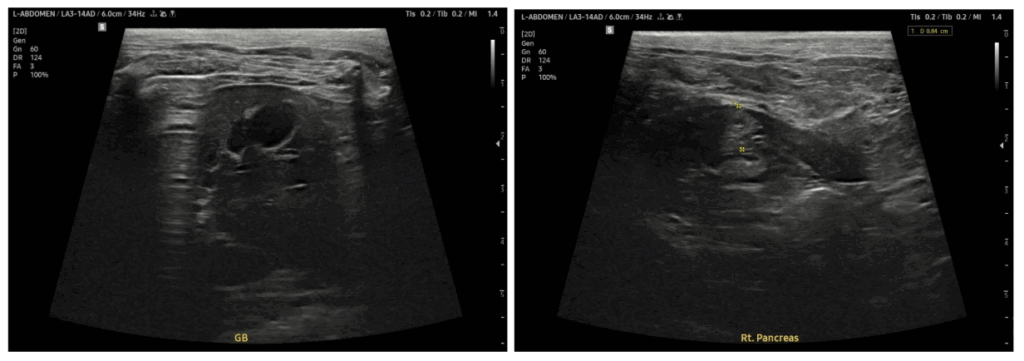

통원치료 전환 후 일주일 뒤 초음파 상 췌장, 담낭벽 비후 개선 보이고 케톤산증 상태 재발 없이 안정적으로 유지되어 현재 정기적인 당뇨 관리 외 치료 종료되었습니다.

재진 복부 초음파 검사 결과

췌장 비후 및 담낭벽 비후 개선 확인